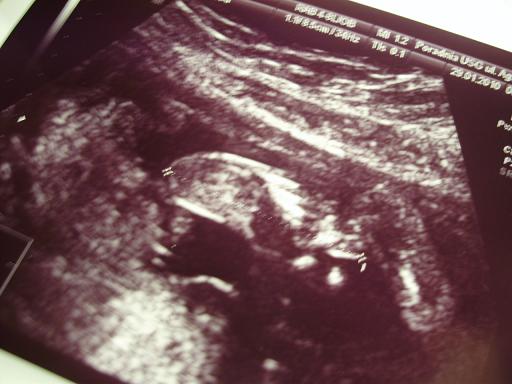

cudeńko